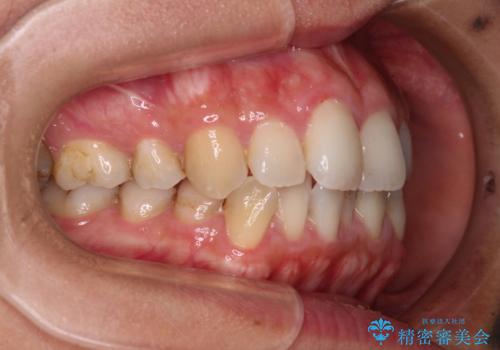

前歯のデコボコを改善 インビザラインの矯正治療

- 前歯のデコボコを治したいとのことで来院された患者様です。

上下顎ともに歯列全体の後方移動とIPR(歯と歯の間を削る)によってデコボコが解消するように設計し、インビザラインにより治療を行うこととしました。